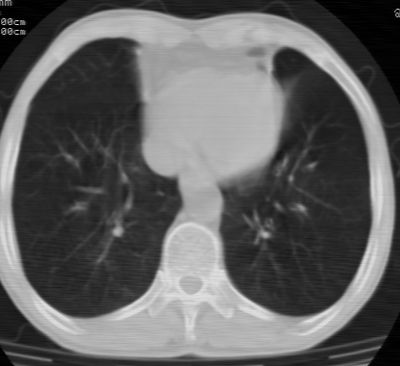

标题: CT24783:m71,既往肺心病史3年,现咳嗽,憋喘。 [打印本页]

标题: CT24783:m71,既往肺心病史3年,现咳嗽,憋喘。

1、左肺上叶spn,毛刺+分叶+血管集束征,考虑周围型肺癌可能性大

2、全小叶性肺气肿。

1)左肺上叶周围型肺癌可能。2)两肺全小叶型肺气肿。

左上周围型肺癌,全小叶型肺气肿。